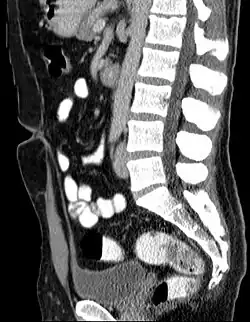

L’ouraque est un cordon fibreux joignant le pôle antéro-supérieur de la vessie à l'ombilic.

L'ouraque est un cordon fibreux creux mais borgne (fermeture physiologique des deux extrémités) présent dans l'abdomen, chez l'humain, et reliant la vessie à l'ombilic. C'est le vestige du canal allantoïdien, qui relie chez l'embryon le cloaque au cordon ombilical, et qui régresse à partir de la 6e semaine ; sa fermeture est normalement complète à la naissance.

- Kyste de l'ouraque : n'est une pathologie qu'en cas de complications infectieuses